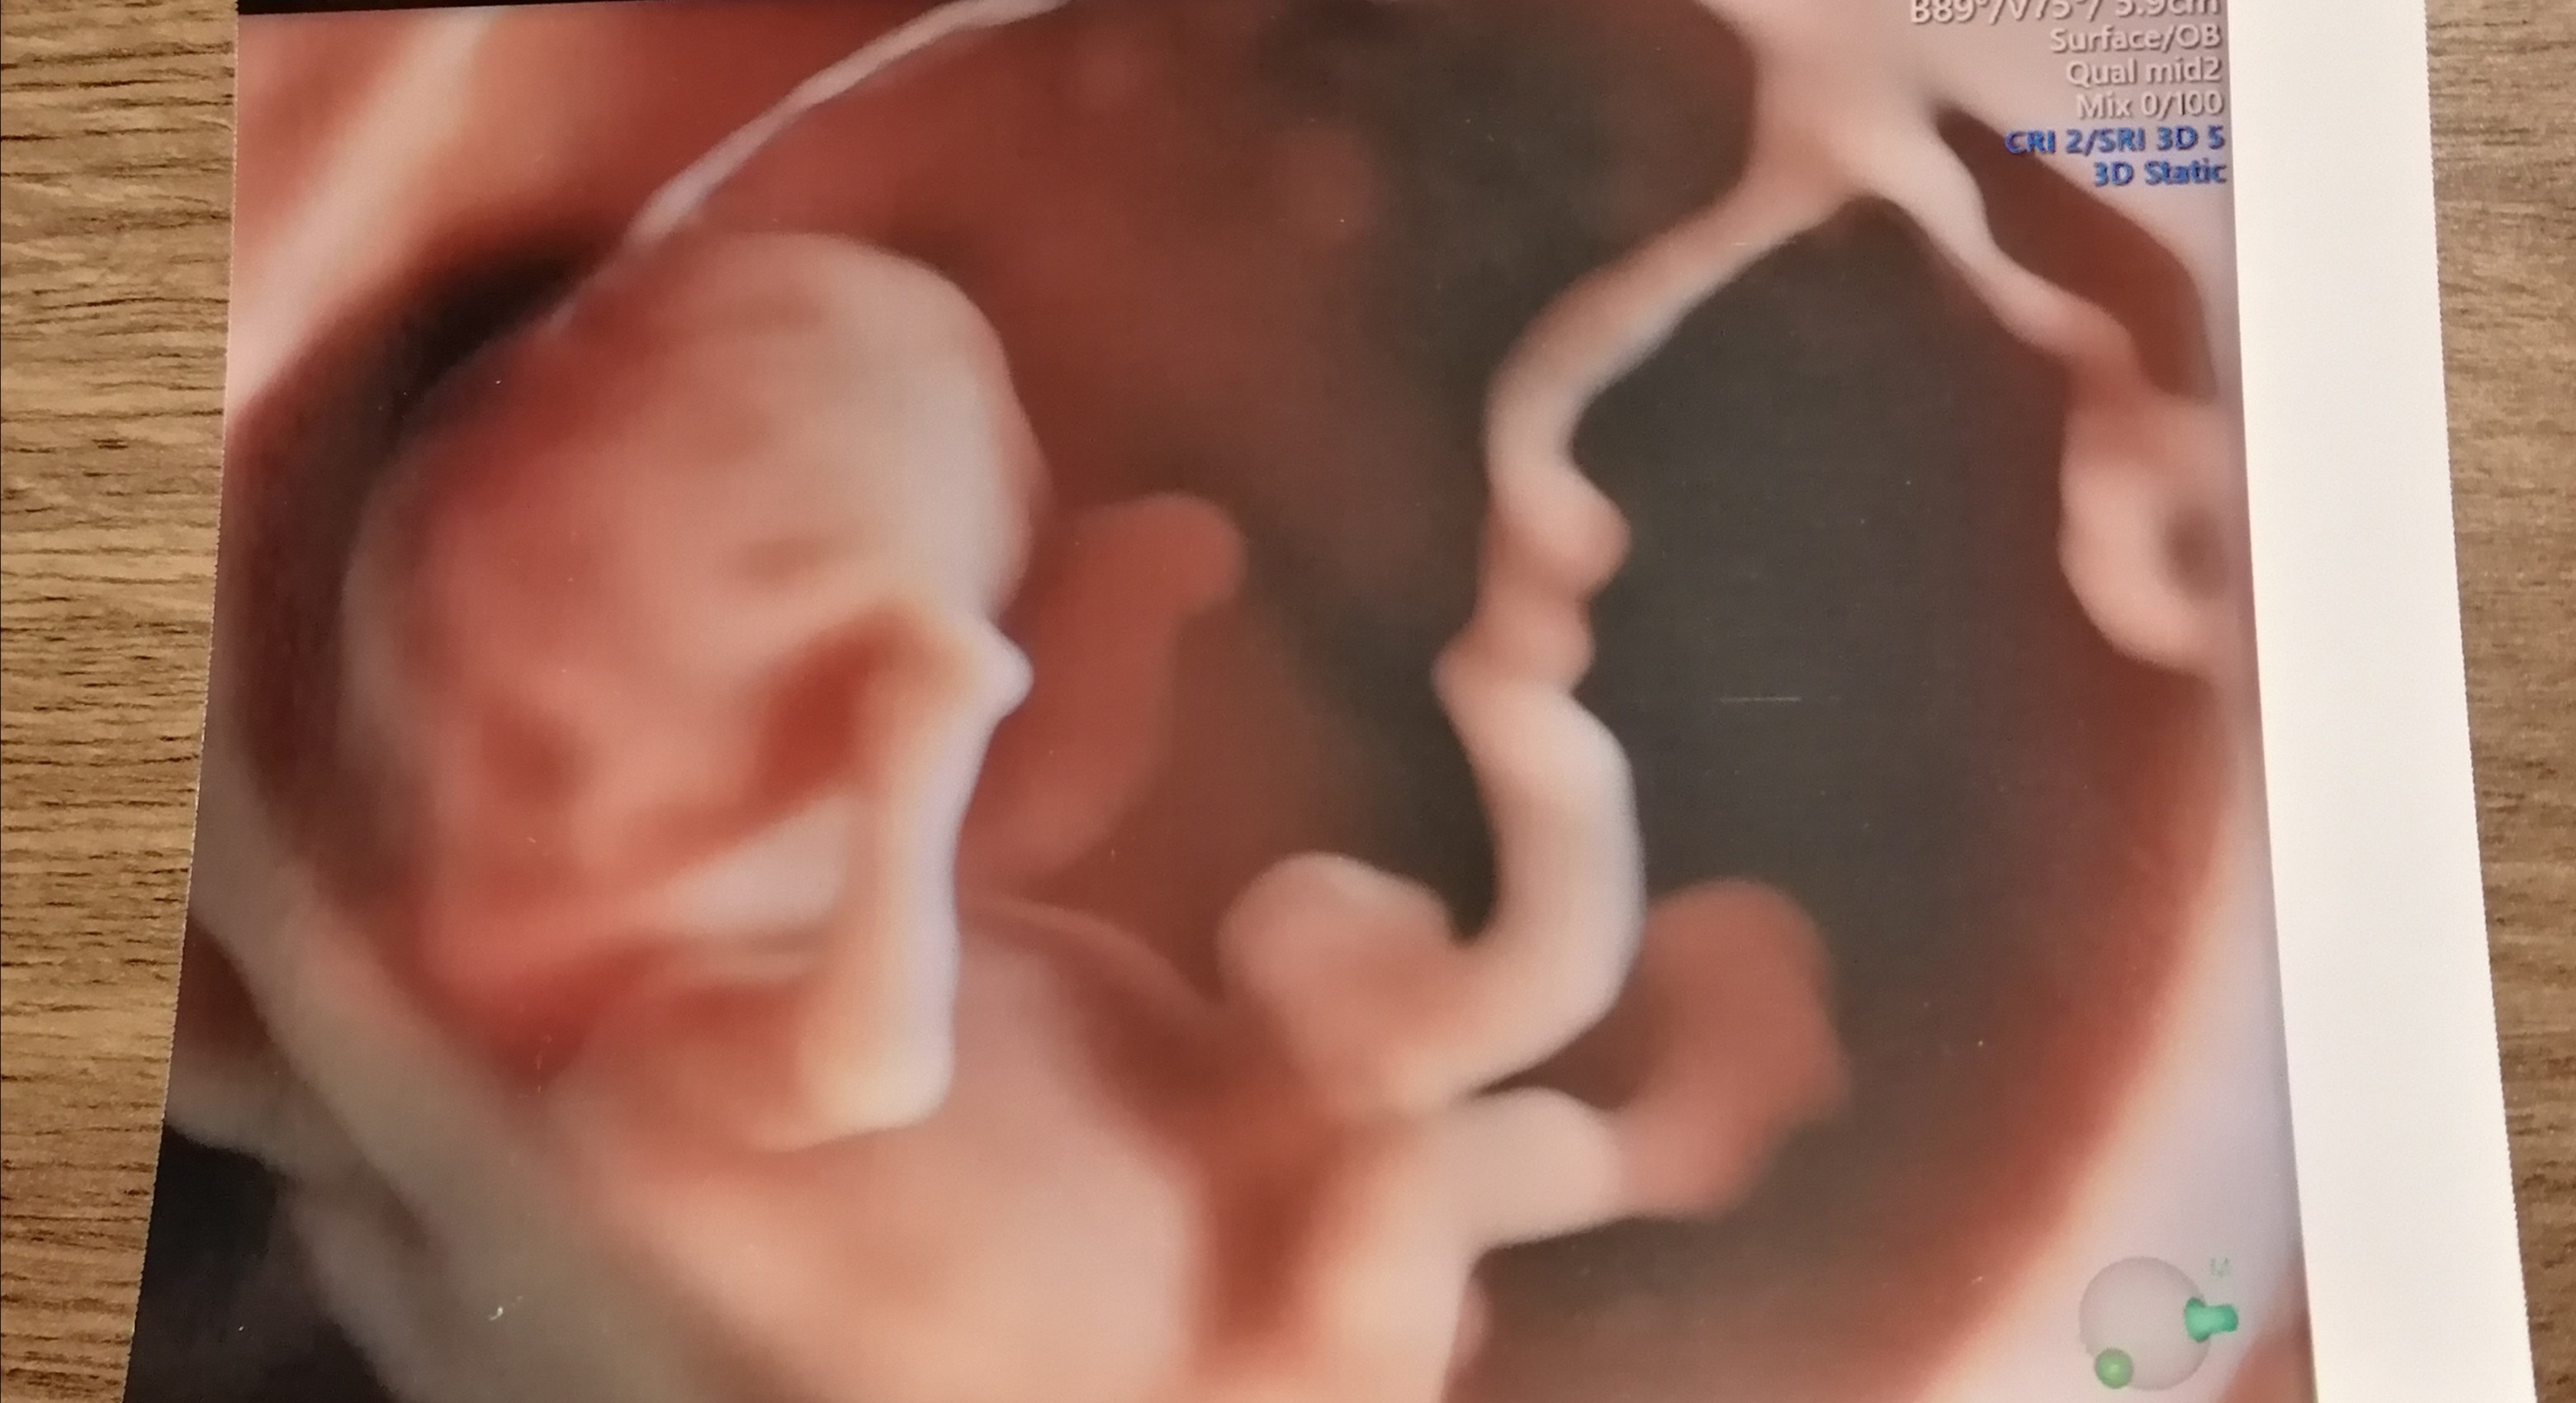

Zobacz załącznik 1123423

Z poprzedniego USG mi wychodzi 10+2, ale na obecnym mam 11+1, czyli tak jakby liczyło z OM, sama nie wiem jak to już jest. Tyle miałam pytań do lekarza i z tego wszystkiego ich nie zadałam 🙈

Ooo to moje wyglada podobnie w takim razie 😍 lubie tak patrzec na zdjecia w podobnym tygodniu co jestem zeby sobie wyobrazic jak maluszek wyglada 😅